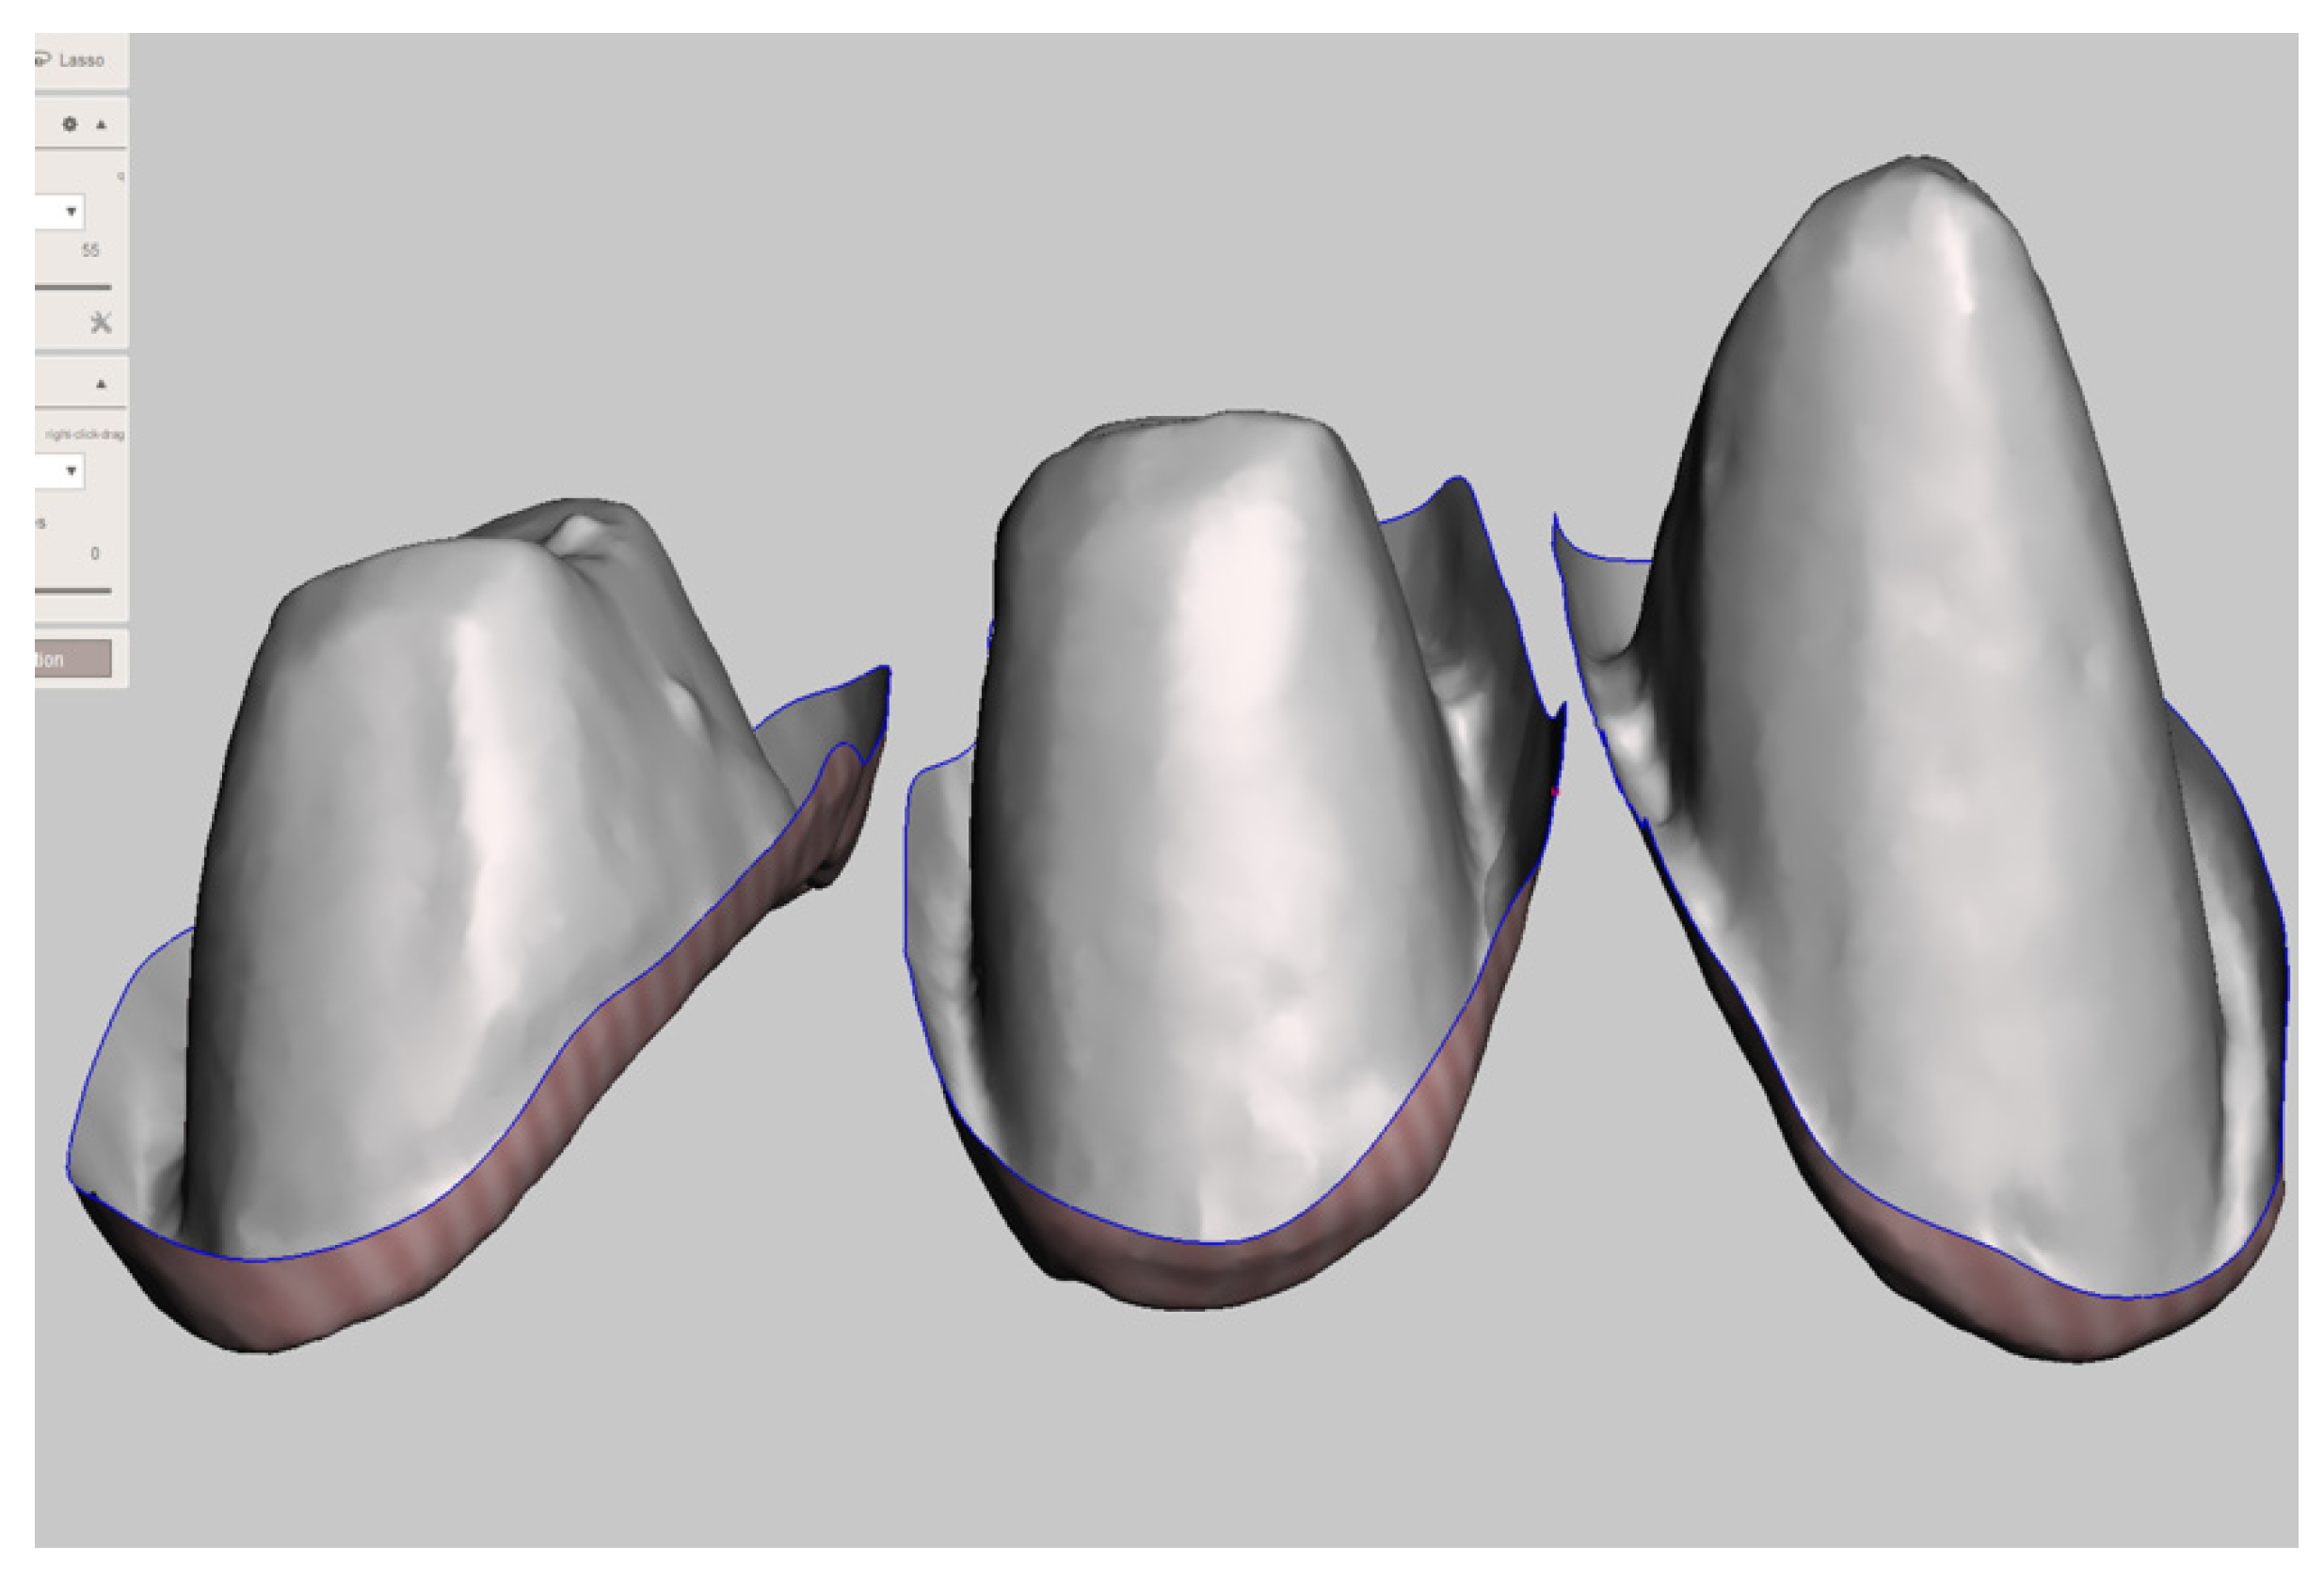

Figure 8.

Selection of unnecessary areas.

Figure 9.

Manipulation of the inside area of the provisional restoration after deleting all unnecessary areas.